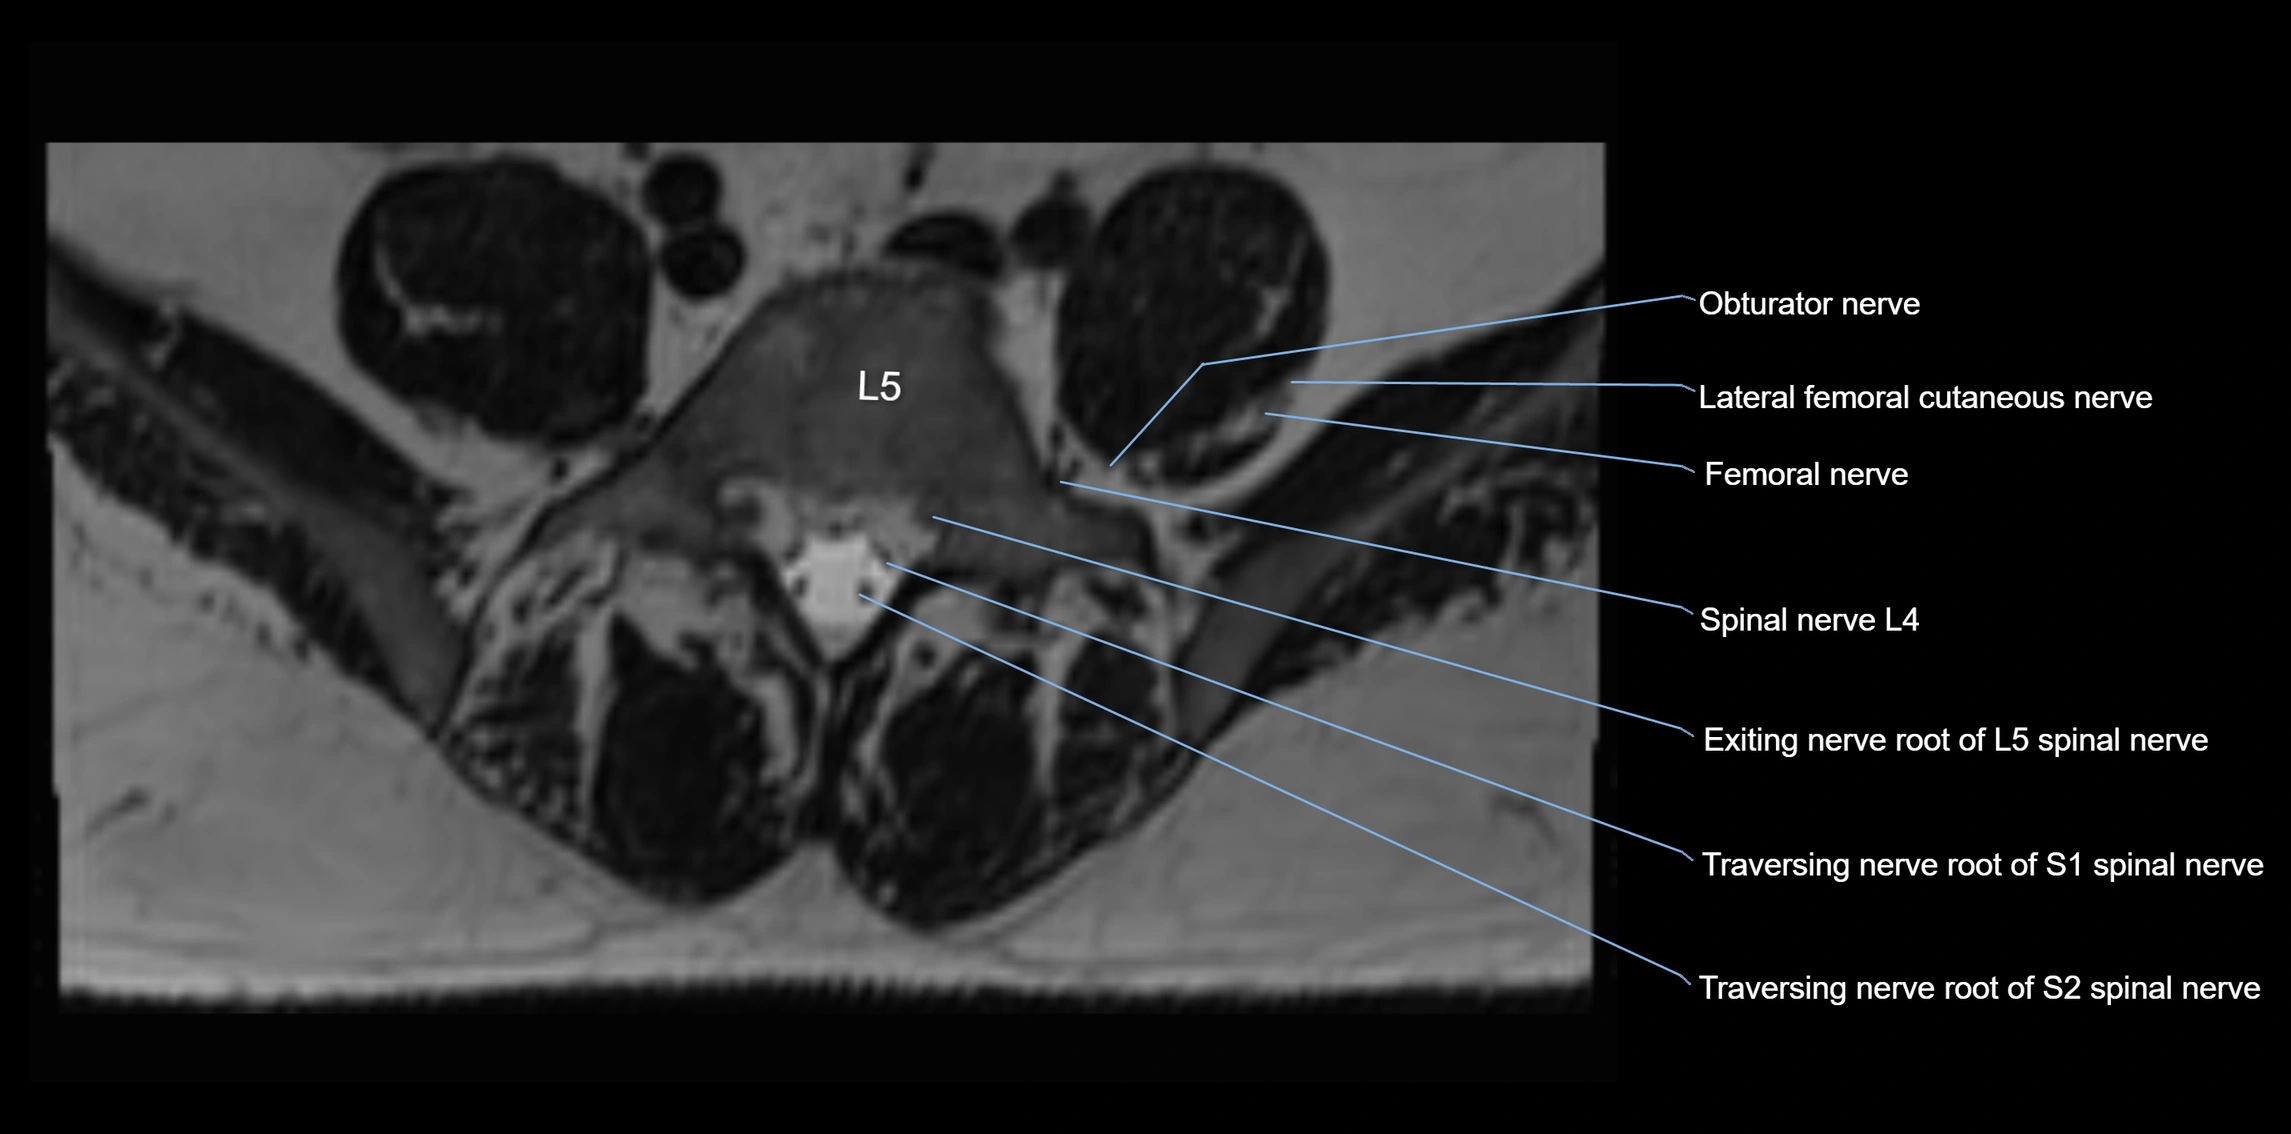

MRI image

image